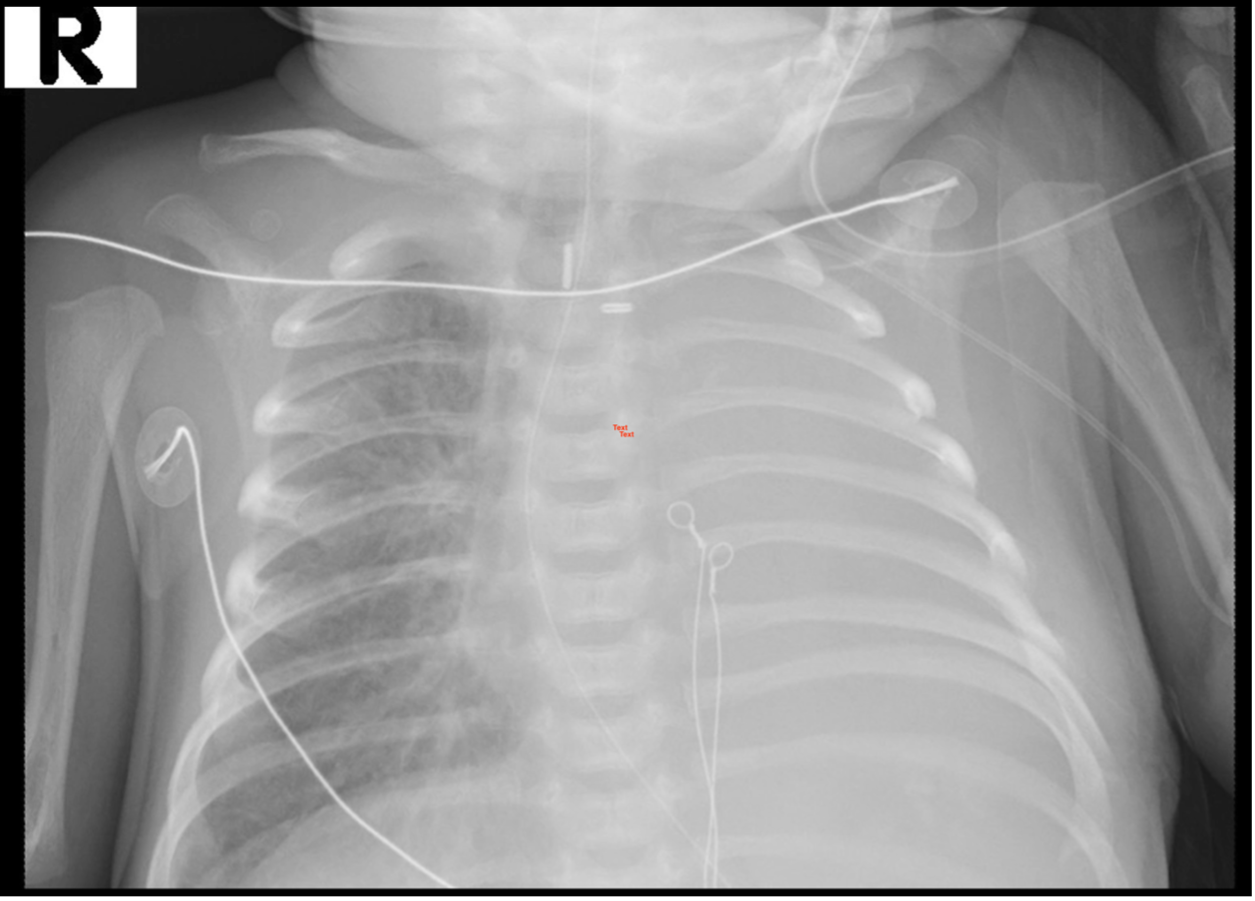

Outcome: Post-procedure imaging confirmed complete aeration of the left lung with no evidence of pneumothorax (figure 4). The neonate was extubated the following day and remained clinically stable. The post-extubation chest x-ray, as well as serial x-rays during the subsequent two weeks demonstrated no recurrence of atelectasis in the left lung.

Chest radiograph following procedure

Figure 4. Chest radiograph following procedure.